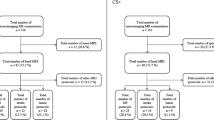

Images from all 50 patients were reviewed by the two study neuroradiologists to evaluate for concordance. Patient demographics are summarized in Table 1. T2W FLAIR with AI had excellent or sufficient imaging quality in 98% (reader 1, 50/50; reader 2, 48/50) of cases and excellent or sufficient diagnostic confidence in 98% (reader 1, 50/50; reader 2, 48/50) of cases. These and other findings are summarized in Fig. 5. When compared with non-AI, 99% (reader 1, 49/50; reader 2, 50/50) of evaluations submitted reported better overall image quality and subjectively improved SNR with AI. 99% (reader 1, 49/50; reader 2, 49/50) of evaluations submitted reported better diagnostic preference with AI compared with non-AI. When comparing standard versus AI-reconstruction, the degree of artifacts related to cerebrospinal fluid (CSF) pulsation and magnetic susceptibility were the same in 100% (readers 1 and 2, 50/50) of patients. Motion artifacts were the same in 98% (reader 1, 49/50; reader 2, 49/50) of patients. These and other findings are summarized in Table 1.

Pathology or normal variants were observed in the standard reconstruction images by the principal investigator in 42% (21/50) of patients and were reproduced in all cases on the AI images; the remaining 58% (29/50) of exams were interpreted as normal and study interpretations were subsequently compared to the official clinical reports to exclude the possibility of overlooked clinically relevant pathology. Pathologies identified included foci of presumed gliosis (n=6), Chiari I (n=2), mild ventriculomegaly (n=1), arachnoid cysts (n=1), dolichocephaly (n=1), cystic encephalomalacia (n=1), tuberous sclerosis (n=1), and a right thalamic mass (n=1). Normal variants included mega cisterna magna (n=2), cerebellar developmental venous anomaly (n=1), enlarged perivascular spaces (n=1), and cerebellar ectopia not meeting criteria for Chiari I (n=1). No additional anomalies were identified on the AI images by either radiologist.